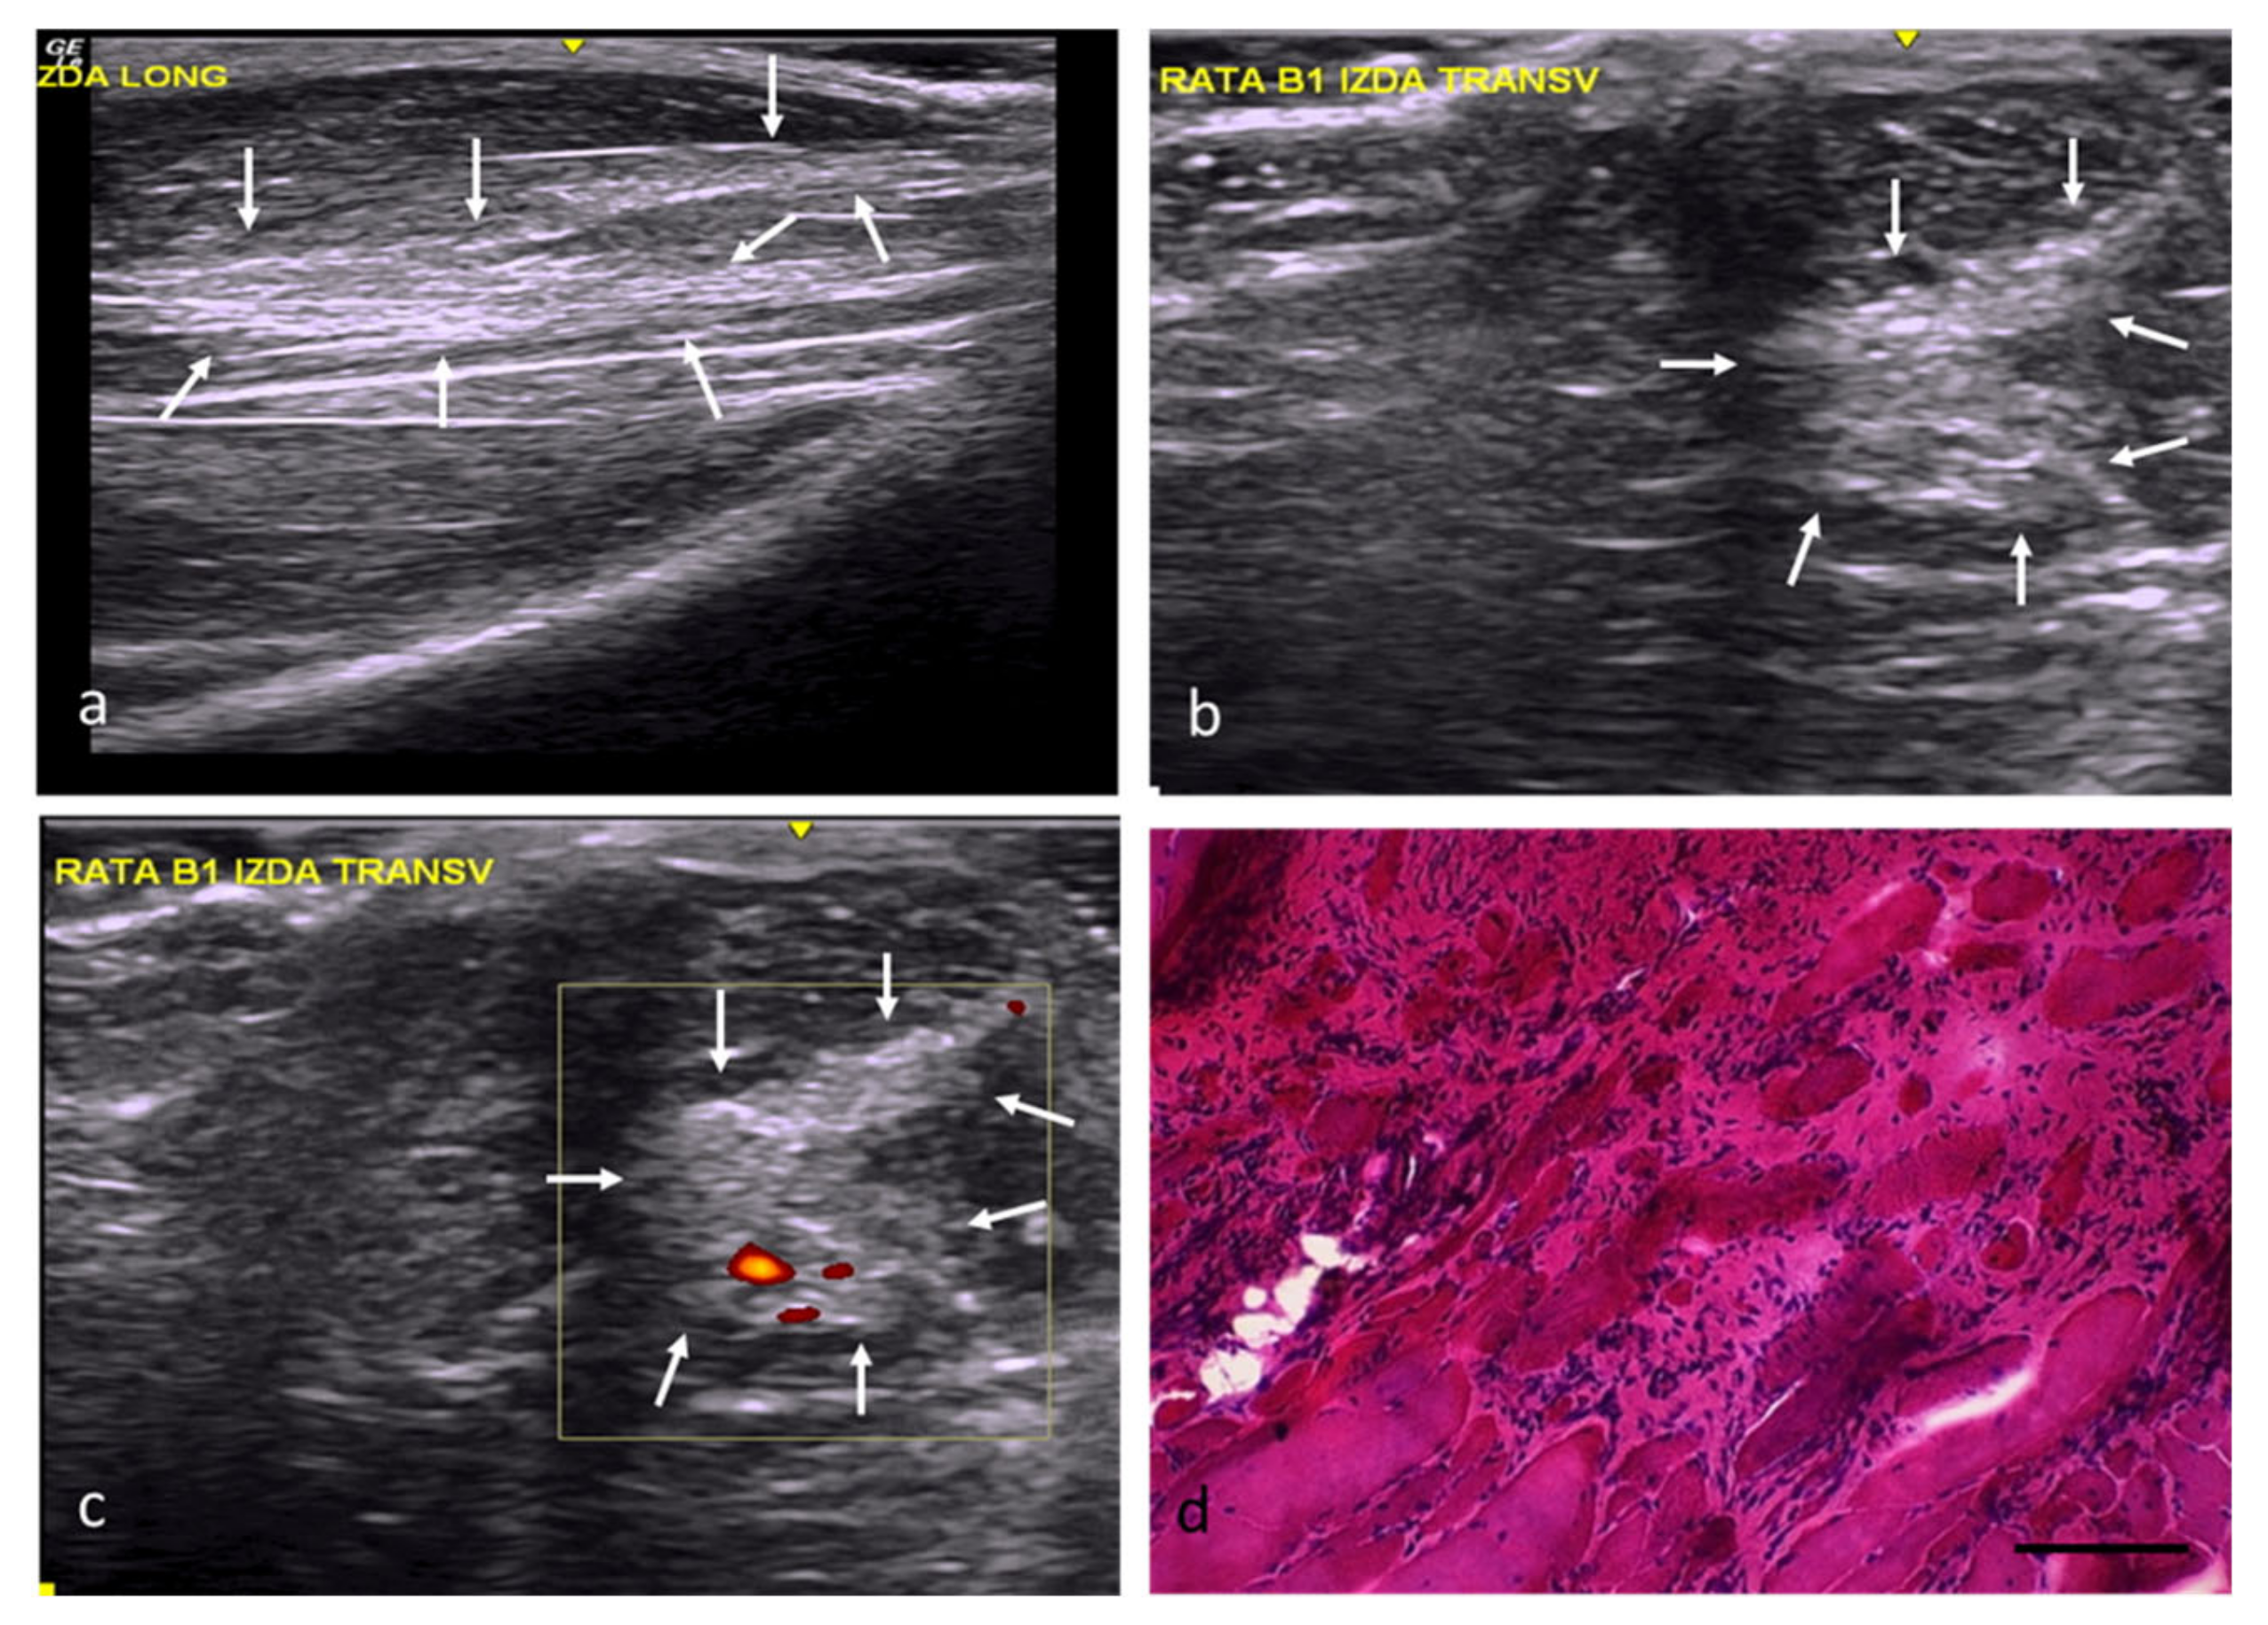

In the RC group, the injury areas could be identified, but their margins were imprecise and poorly defined, with a slightly distorted echostructure, somewhat increased echogenicity, and moderately increased vascularization (Figure 2a–c). In this study group, the muscles’ histological features were practically normal, except for internal nuclei (Figure 2d) and some minimal changes (Table 2).

Figure 2.

RC group. (a) Longitudinal section, with images of a slightly hyperechoic injury compared with the adjacent muscle tissue and a distorted fibrillar pattern, demarcated by white arrows. (b) Transverse section, with images of an injury with slightly increased echogenicity and poorly defined margins, demarcated by white arrows. (c) Transverse section assessed by power Doppler imaging, with images of moderately increased perilesional vascularization. (d) Transverse section representative of the muscle histology. H-E. Size scale: 100 µm.

In the FC group, the injuries had an angular morphology, were well defined, and had slightly increased echogenicity, a clearly distorted echostructure, and slightly increased vascularization (Figure 3a–c). From a histological point of view, 74% of the area of the muscle defects in this group was occupied by fibroadipose tissue (Figure 3d). The scarce number newly formed fibers, some with internal nuclei, were relegated to the injuries’ margins (Figure 3d).

Figure 3.

FC group. (a) Longitudinal axis, with images of a hyperechoic area compared with the normal muscle tissue and a distorted echostructure, demarcated by white arrows. (b) Transverse axis, with images of a well-defined injury with angular margins and increased echogenicity. (c) Transverse section assessed by power Doppler imaging, with images of a slight, predominantly peripheral, increase in vascularization. (d) Transverse section representative of the muscle histology. H-E. Size scale: 100 µm.